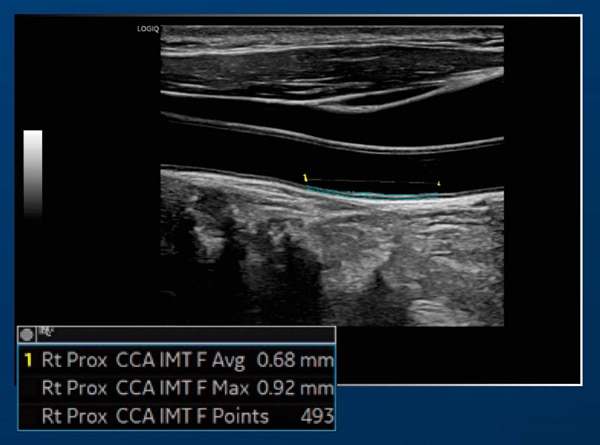

Auto IMT

自動で簡単にIMTを計測可能。

IMT-C10の計測もサポートし、検査の効率化に貢献します。